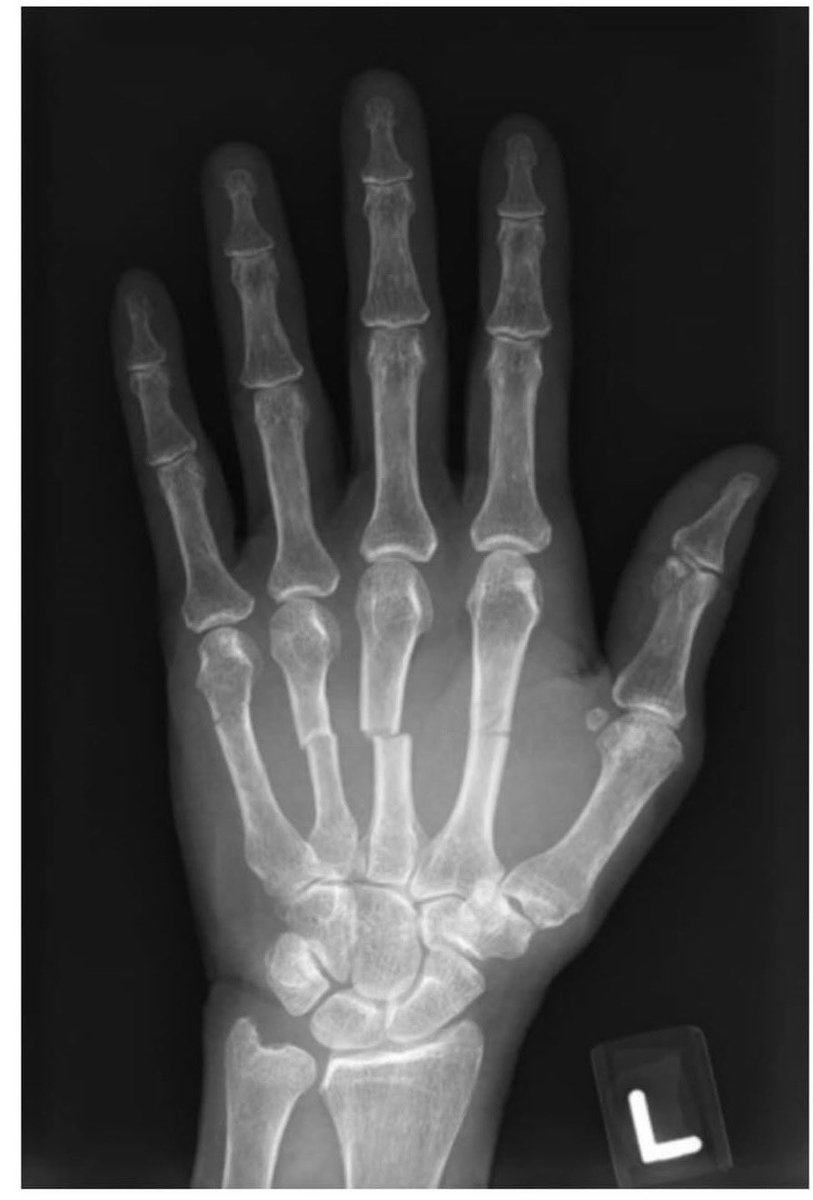

@Sage_medics 3. But you need lateral view to confirm that the 5th

Metacarpal phalanx is intact